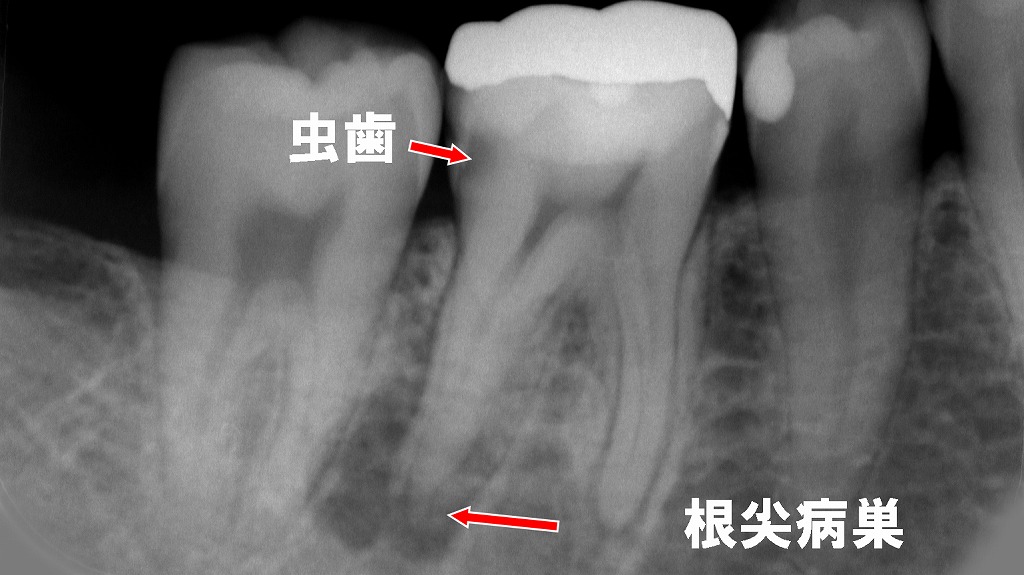

下顎6番は遠心に深い虫歯が進行し、歯髄が細菌感染した結果、根尖部には透過像として根尖病巣が認められました。そのため、感染した歯髄を除去し根管内を清掃・消毒する抜髄処置を行い、4根管すべてに対して根尖まで適切に根管充填を行いました。レントゲンでは各根管に充填材が連続的に満たされ、根尖まで良好に封鎖されていることが確認できます。これにより再感染のリスクを抑え、歯の保存が可能な状態へと整えられています。